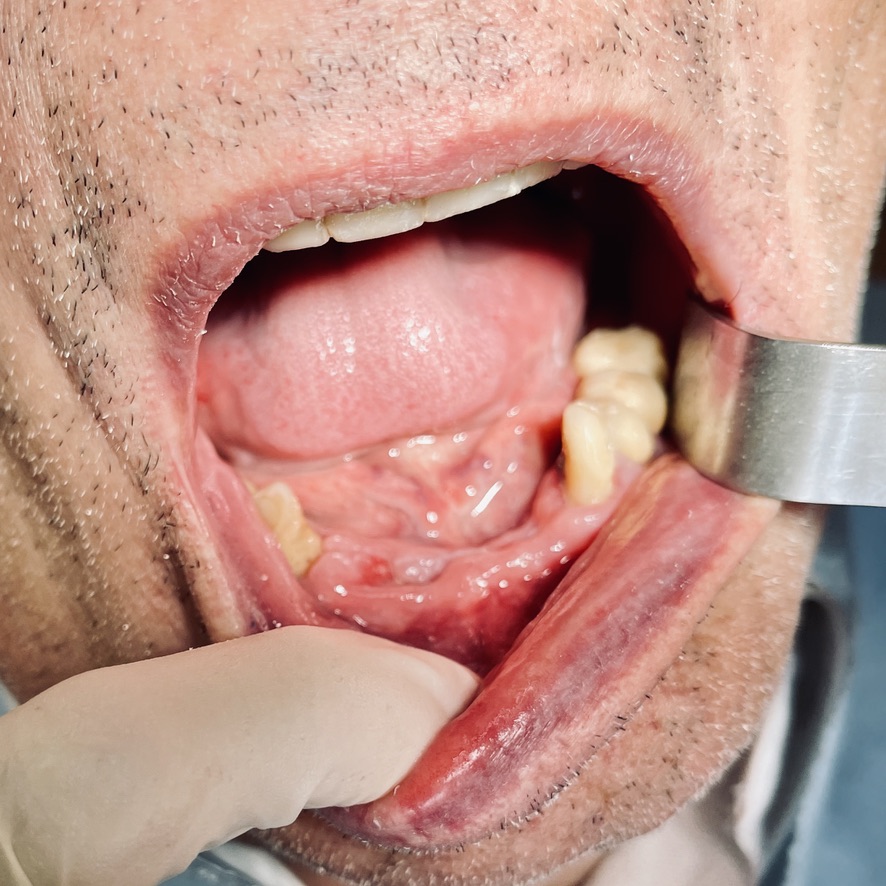

CLINICAL CASE combined with news n.6. Rehabilitation of 04/28/2021

In particular, I consider the following aspects to be significant:

• 1 Age of the patient: 83 years old

• 2 Execution of the first 6 plants: 25 years ago.

• 3 Execution of the 5 subsequent plants: 14 years ago

• 4 Medicines taken by the patient: none

• 5 Presence of implants in the tuber / pterygoid area

• 6 Presence of ancient inclined implants

• 7 Presence of implant bent in 25. (To parallelize it)

• 8 Presence of two mini-plants in 11-12

• 9 Presence of a welded bar in the upper sector

• 10 Severe periodontal disease of the lower sector

• 11 Hygiene issues

• 12 Implant failure of lower Tramonte implant, implant prior to 2004, in the context of general periodontal disease

• 13 The insertion of the three implants did not involve bone or connective tissue grafts

• 14 It did not make detachments necessary

• 15 It was not necessary to isolate the emergencies of the inferior alveolar nerves

• 16 Since we are dealing with high-density bone, we resorted to the helical drill, an instrument rarely used by us because it is not necessary and because there are areas where its use involves surgical risks that are not acceptable to us. In addition, this drill removes discrete amounts of bone that we prefer to remain where nature has put it. It is interesting that the diameter of the cutter is only 2 mm

• 17 Being dense bone, the implants used had a diameter of only 4 mm after tapping with the corresponding tap

• 18 At the check-up on 3/5/2021 the patient is not swollen and reports that he is finally eating well

• 19 Implant surgery starts at 8.45am. end of implant surgery at 9.36

• 20 Cementation of the provisional, packaged at the moment, completed at 10.30. total length of stay of the patient in the clinic 1.45 hours.

The images provide additional information in the captions.